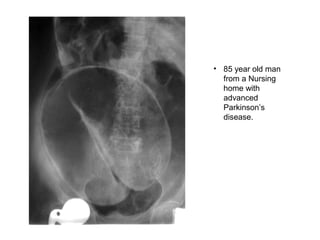

• 85 year old man

from a Nursing

home with

advanced

Parkinson’s

disease.

• 85 yearold man from a Nursing home with advanced Parkinson’s disease.